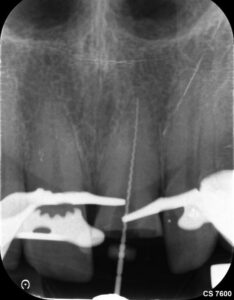

Das Zahnfragment hatte eine gute Passung auf den frakturierten Stumpf. So konnte im Vorfeld ein Silikonabdruck als Vorwall für den Kompositaufbau erstellt werden. Die endodontische Therapie sowie der Füllungsaufbau erfolgten ausschließlich unter dem hochauflösenden OP-Mikroskop (Zumax OMS2350). Die zu behandelnde Region wurde mit Ubistesin 1/200000 lokal betäubt. Anschließend wurde von 11 bis 22 ein Kofferdam angebracht. Der Zahn wurde mit einem konischen Diamanten trepaniert, die Trepanationsöffnung mit Gates-Glidden-Bohrern erweitert. Die Aufbereitung erfolgte mit dem Reciproc Blue System bis zur Größe 50.05.

Es wurde mit 15 Milliliter Natriumhypochlorid und 2,5 Milliliter EDTA gespült. Beide Flüssigkeiten wurden mittels PUI (assive Ultrasonic Irrigation) aktiviert.

Die Wurzelfüllung erfolgte in Continuus Wave Technik und Backfill in zwei Inkrementen mit

Guttapercha und AH Plus als Sealer. Anschließend wurden aufgrund der ovalen Kavität zwei Glasfaserstifte zur Stabilisation der Füllung eingebracht und mit Luxacore adhäsiv verklebt.